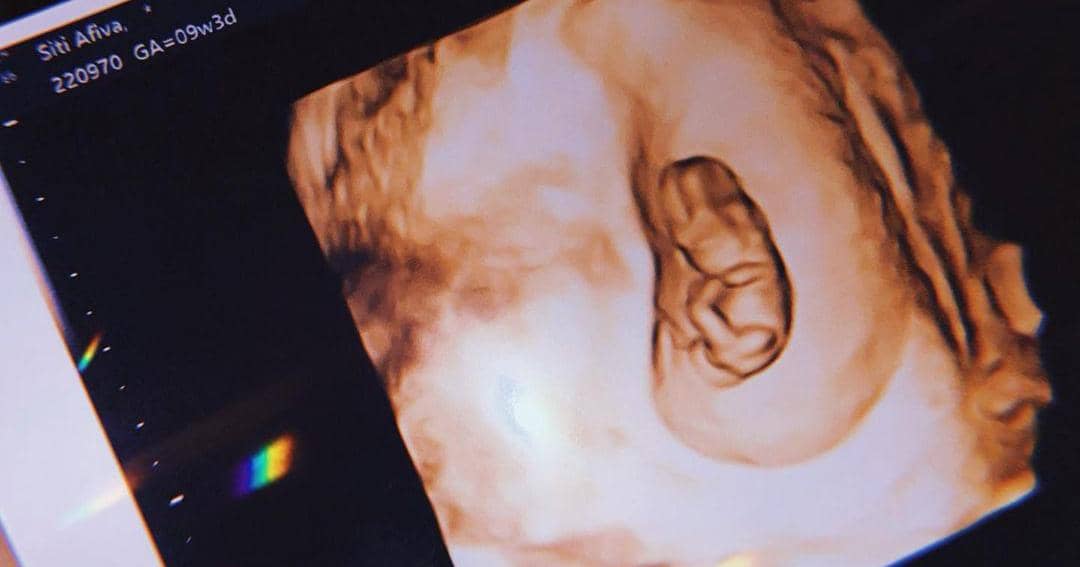

Rosiana pertama kali mengumumkan kabar kehamilannya pada 20 September 2021. Ia dan Handika kompak membagikan foto hasil USG calon buah hati yang selama ini mereka tunggu-tunggu.

Berselang beberapa minggu kemudian, Rosiana juga menguggah foto USG janin di kandungannya yang saat itu masih berusia 9 minggu. Banyak warganet dan rekan artis menuliskan ucapan selamat sekaligus mendoakan kesehatan calon bayi.